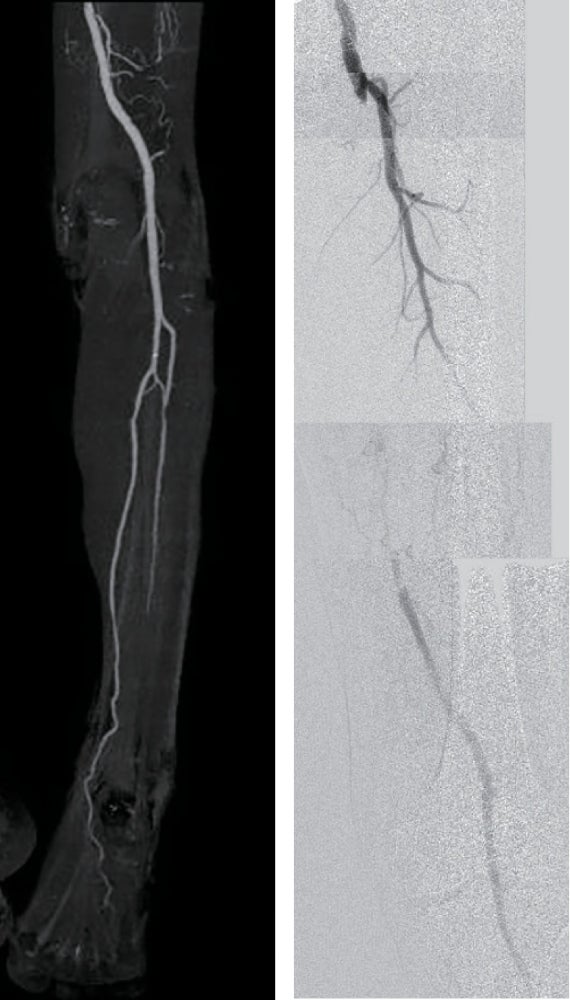

- 径6.0/長150 mm高圧バルーンにて高圧拡張を追加し、DFAの血流も問題がないことを確認して手技終了(図5)。

他院でシロスタゾールを開始され保存的経過観察となっていた症例で、Class 2–3の間欠性跛行残存に対する積極的治療希望にてEVTを行ったが、EVT後2年以上を経過した現在まで良好な経過を辿っている。

治療前後の造影動画